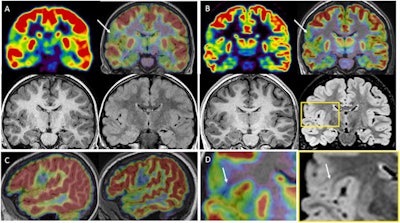

The group found that MRI was initially considered negative in 21 patients. Standalone PET identified abnormalities in 19 cases (76%) and detected four additional structural lesions when fused with MRI imaging. Compared with the fused PET and MRI scans, hybrid PET/MRI sensitivity increased by 13% and identified new structural lesions (mainly focal cortical dysplasias) in six patients (24%).

In addition, hybrid PET/MRI resulted in changes in surgical decisions for 10 patients (40%), consisting of avoiding invasive monitoring in six patients and modifying the planning in four others, the researchers found.